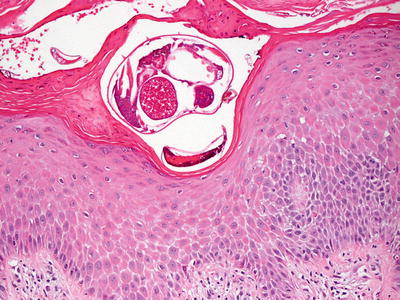

Fig. 14.3

Entire mites are readily observed at the base of the stratum corneum in some cases of scabietic infestation